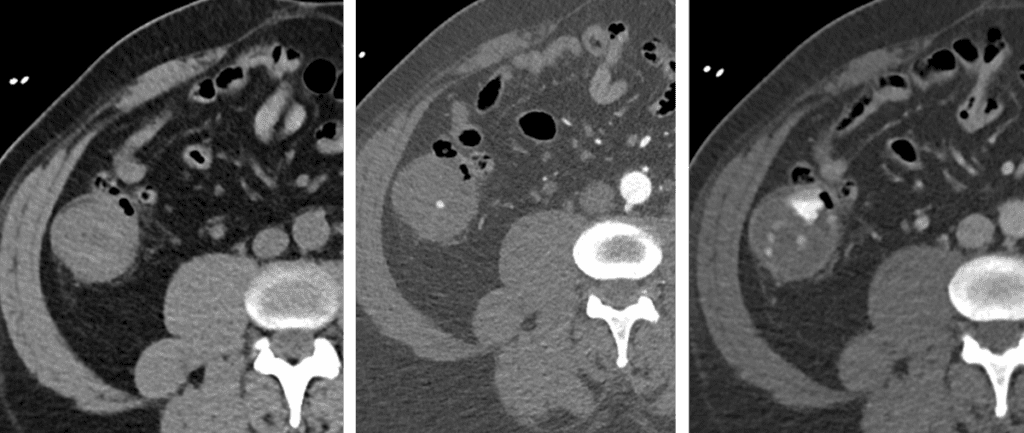

Active GI Bleed on CTA

Arterial extravasation that increases on delayed phase is diagnostic of active bleeding.

• CTA is exam of choice to diagnose acute GI bleeding – quickly replacing tagged RBC scans.

• CTA protocol: No oral contrast, must include non con, arterial and venous phase imaging.

• Non contrast imaging is key to avoid false positives.

• Faster diagnosis = improved embolization success.

Bell iconMultiphase CTA = Faster, more specific, better anatomic localization.